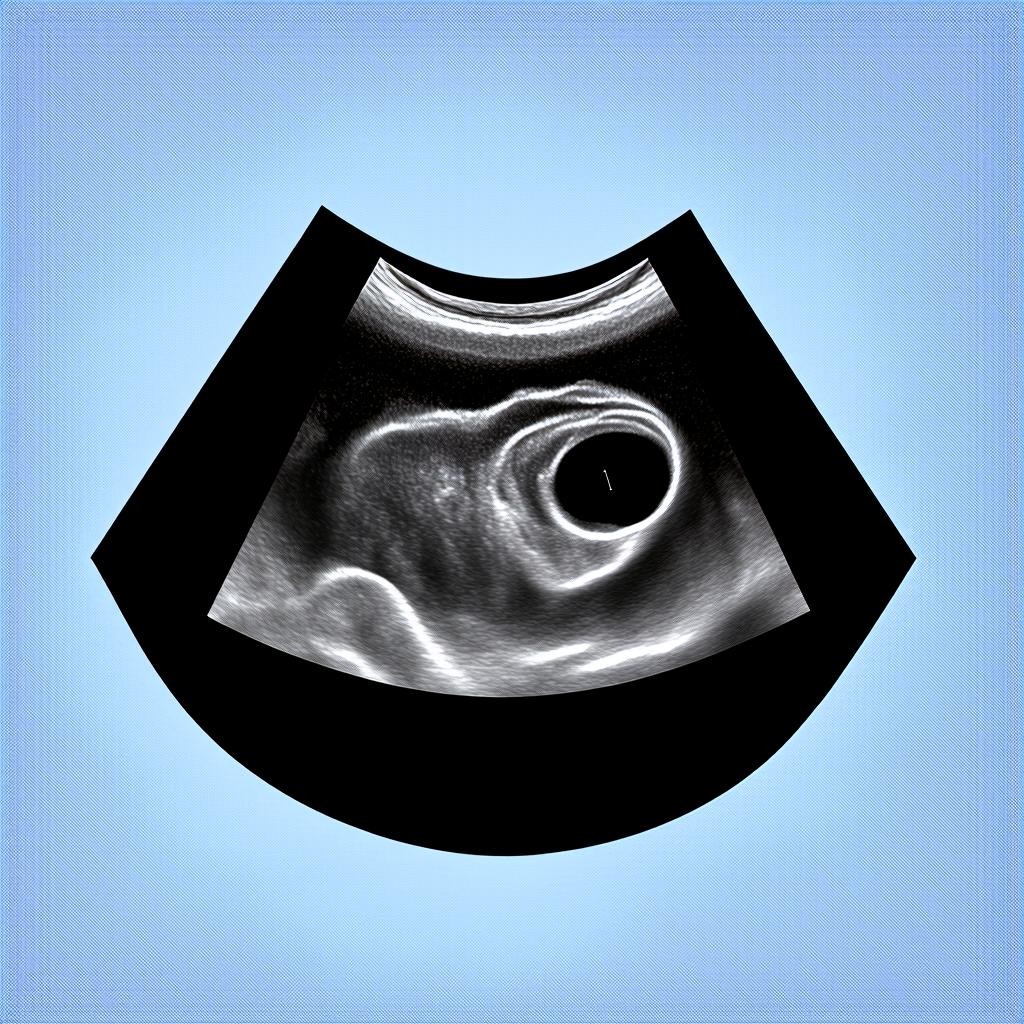

Один из самых распространенных источников тревоги и недопонимания на ранних сроках — расхождение между календарным и эмбриологическим методом подсчета. В акушерской практике срок беременности традиционно отсчитывается от первого дня последней менструации (акушерский срок), а не от даты зачатия (эмбриональный срок). Таким образом, на момент «4 недели беременности» по календарю женщины, реальный возраст эмбриона с момента оплодотворения составляет всего около 2 недель. Именно этот факт является ключевым для интерпретации результатов ультразвукового исследования. В этот период только начинает формироваться гестационный (плодный) мешок, а визуализация самого эмбриона и его сердечной деятельности — задача для оборудования экспертного класса и более поздних сроков.

Медицинский протокол четко определяет ожидания для каждого этапа. На 4-й акушерской неделе, соответствующей примерно 2-й эмбриональной неделе, происходит имплантация бластоцисты в эндометрий и начинается выработка хорионического гонадотропина (ХГЧ). Основные структуры, которые теоретически может обнаружить трансвагинальный датчик высокого разрешения, — это утолщенный эндометрий и, возможно, анэхогенное образование (гестационный мешок) диаметром всего 2-3 мм. Ожидать увидеть эмбрион или желточный мешок на этом этапе — значит предъявлять к диагностике завышенные, не соответствующие биологической реальности требования.

Существует устойчивое заблуждение, что современные ультразвуковые аппараты «видят всё» с самого начала. Это не соответствует действительности. Разрешающая способность даже аппаратов экспертного класса имеет физический предел, определяемый длиной звуковой волны. Структуры размером менее 1-2 мм могут не давать четкого дифференцируемого сигнала. На 4-й акушерской неделе размеры будущего эмбриона исчисляются десятыми долями миллиметра, что находится на границе или за гранью возможностей визуализации.

Биологический фактор вариативности сроков овуляции и имплантации также вносит коррективы. Овуляция может смещаться на несколько дней даже при регулярном цикле, а процесс имплантации бластоцисты занимает время. Поэтому две женщины с одинаковым акушерским сроком в 4 недели и 3 дня могут иметь принципиально разную ультразвуковую картину: у одной уже будет виден мелкий гестационный мешок в полости матки, а у другой — лишь косвенные признаки. Оба сценария могут быть вариантом абсолютной нормы.